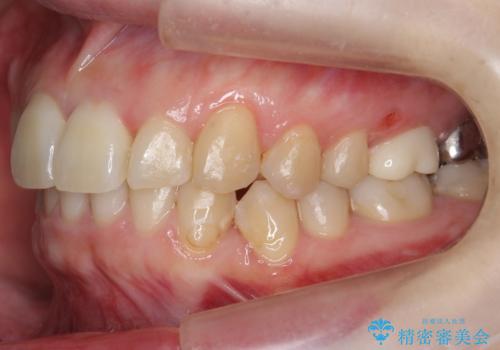

結果それなりに並んで問題ない状況にはなったと思います。

奥歯を後ろに送るために、矯正用ミニスクリューを使用しました。

また、下顎の前歯から奥歯にかけて歯を少し削るIPRを行なっています。